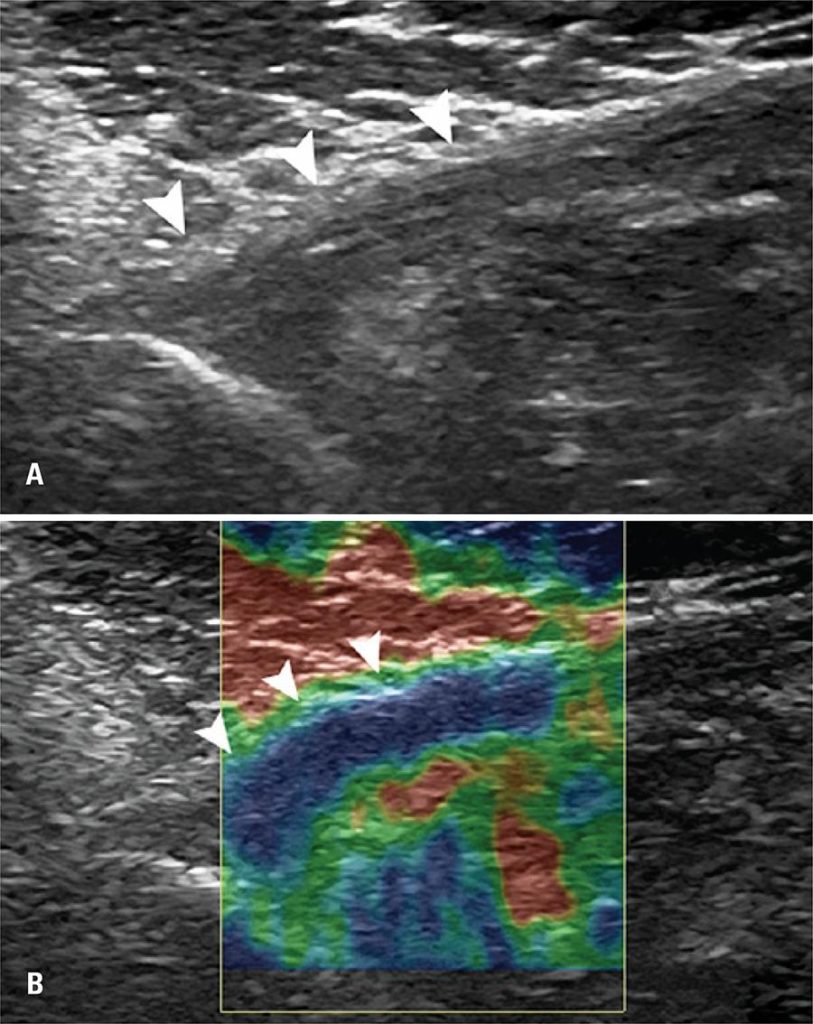

This study included 20 patients, 10 with rupture of the pectoralis major muscle and 10 control patients. We evaluated pectoralis major muscle contralateral tendon with ultrasonographic and elastography examinations. The ultrasonographic examinations were performed using a high-resolution B mode ultrasound device. The elastography evaluation was classified into three patterns: (A), if stiff (more than 50% area with blue staining); (B), if intermediate (more than 50% green); and (C), if softened (more than 50% red).